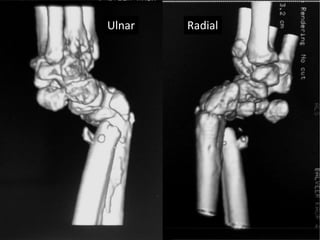

Case two

• 50 years old female

• Low energy injury

• Sustained fracture lower end radius

• Pop cast for six weeks

• Progressively increasing deformity following

removal of plaster.

• X- rays after six months following fracture

showing non-union.

Established non union

Six month old injury

Surgery

• Volar exposure

• Removal of scar tissue and clearing of bone

ends.

• Release of soft tissue contractures.

• Shortening of ulna and plating.

• Plating of radius with bone grafting.